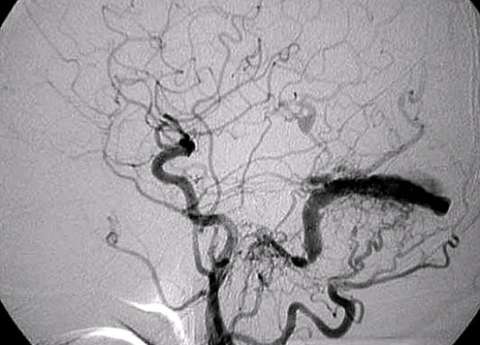

First step of the treatment is to obtain an entire picture of a DAVF and characterize it. Cerebral angiography (dye injection into brain arteries through a plastic tube) is the gold-standard and the most accurate way to do so. Based on the finding of cerebral angiography and the symptoms, the following options are offered:

One of the most worrisome finding is so called "cortical venous reflux". This is the sign that blood flow return to the brain is compromised and associated with high risk of brain hemorrhage. Regardless of the symptoms, DAVF's with cortical venous reflux should be treated as soon as practical by either endovascular embolization or open surgery. Recently, most DAVF's can be treated by endovascular embolization.